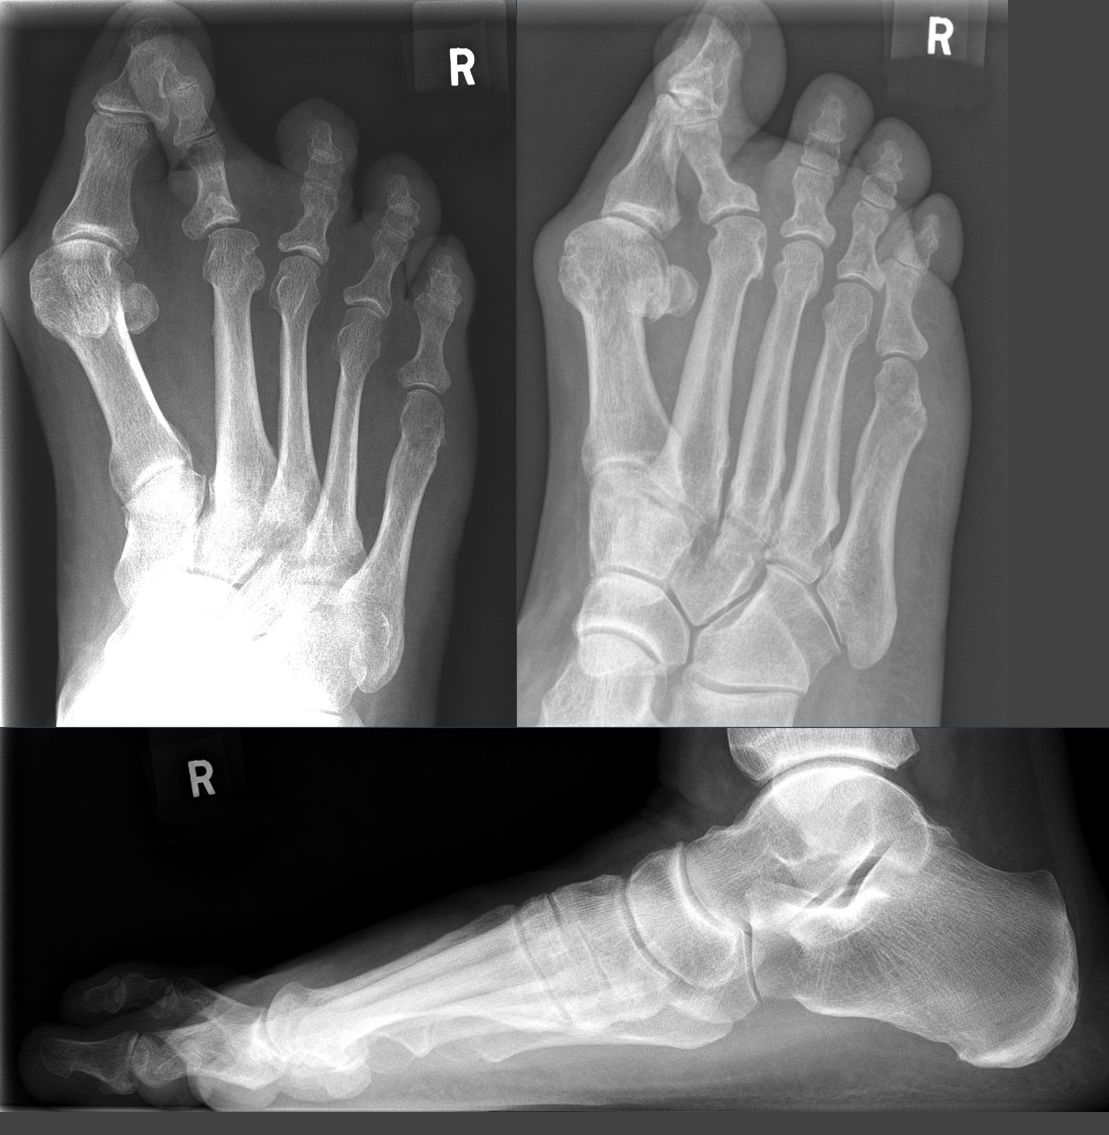

l’hallux valgus